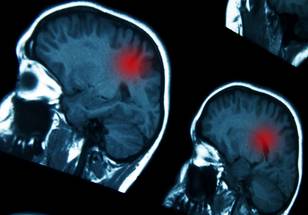

New Review Explores Zika Virus as a Potential Treatment for Brain Cancer

A new review was published in Oncotarget's Volume 15 on September 30, 2024, entitled, "Zika virus and brain cancer: Can Zika be an effective treatment for brain cancer? A systematic review."

As highlighted in the introduction of this review, many studies have identified oncolytic viruses as a promising new class of therapeutic agents for central nervous system (CNS) tumors, particularly glioblastomas (GBM). Zika virus (ZIKV) proteins, specifically targeting certain stem cells, have shown promising results in both in vitro and animal model studies.

The 14 studies demonstrated that ZIKV reduced cell viability, inhibited the growth and proliferation of glioma stem cells (GSCs), and decreased Bcl2 expression, potentially enhancing chemotherapy and radiotherapy effects. ZIKV caused cytopathic effects, induced tumor cell damage, showed oncolytic properties, and selectively killed GSCs safely. This ultimately led to significant tumor remission and improved long-term survival through an enhanced T-cell response.